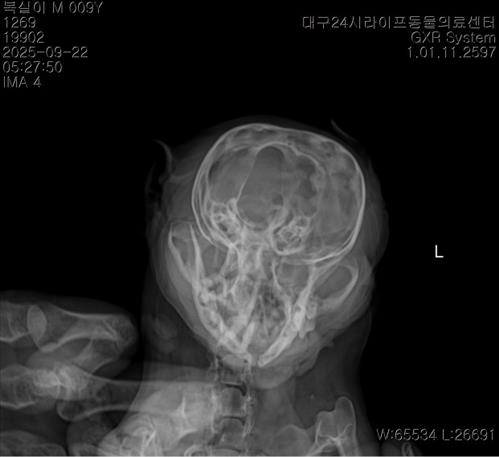

치와와 8세 / 뇌관련 증상

뇌쪽으로 문제가 있다고 알려주시면서 3일치 약을 처방해주셨어요ㅠ 수술을 하는게 좋지만 할수 없는 상황이라면 약 먹여보면서 지켜보는 방법도 있다고 알려주셨는데